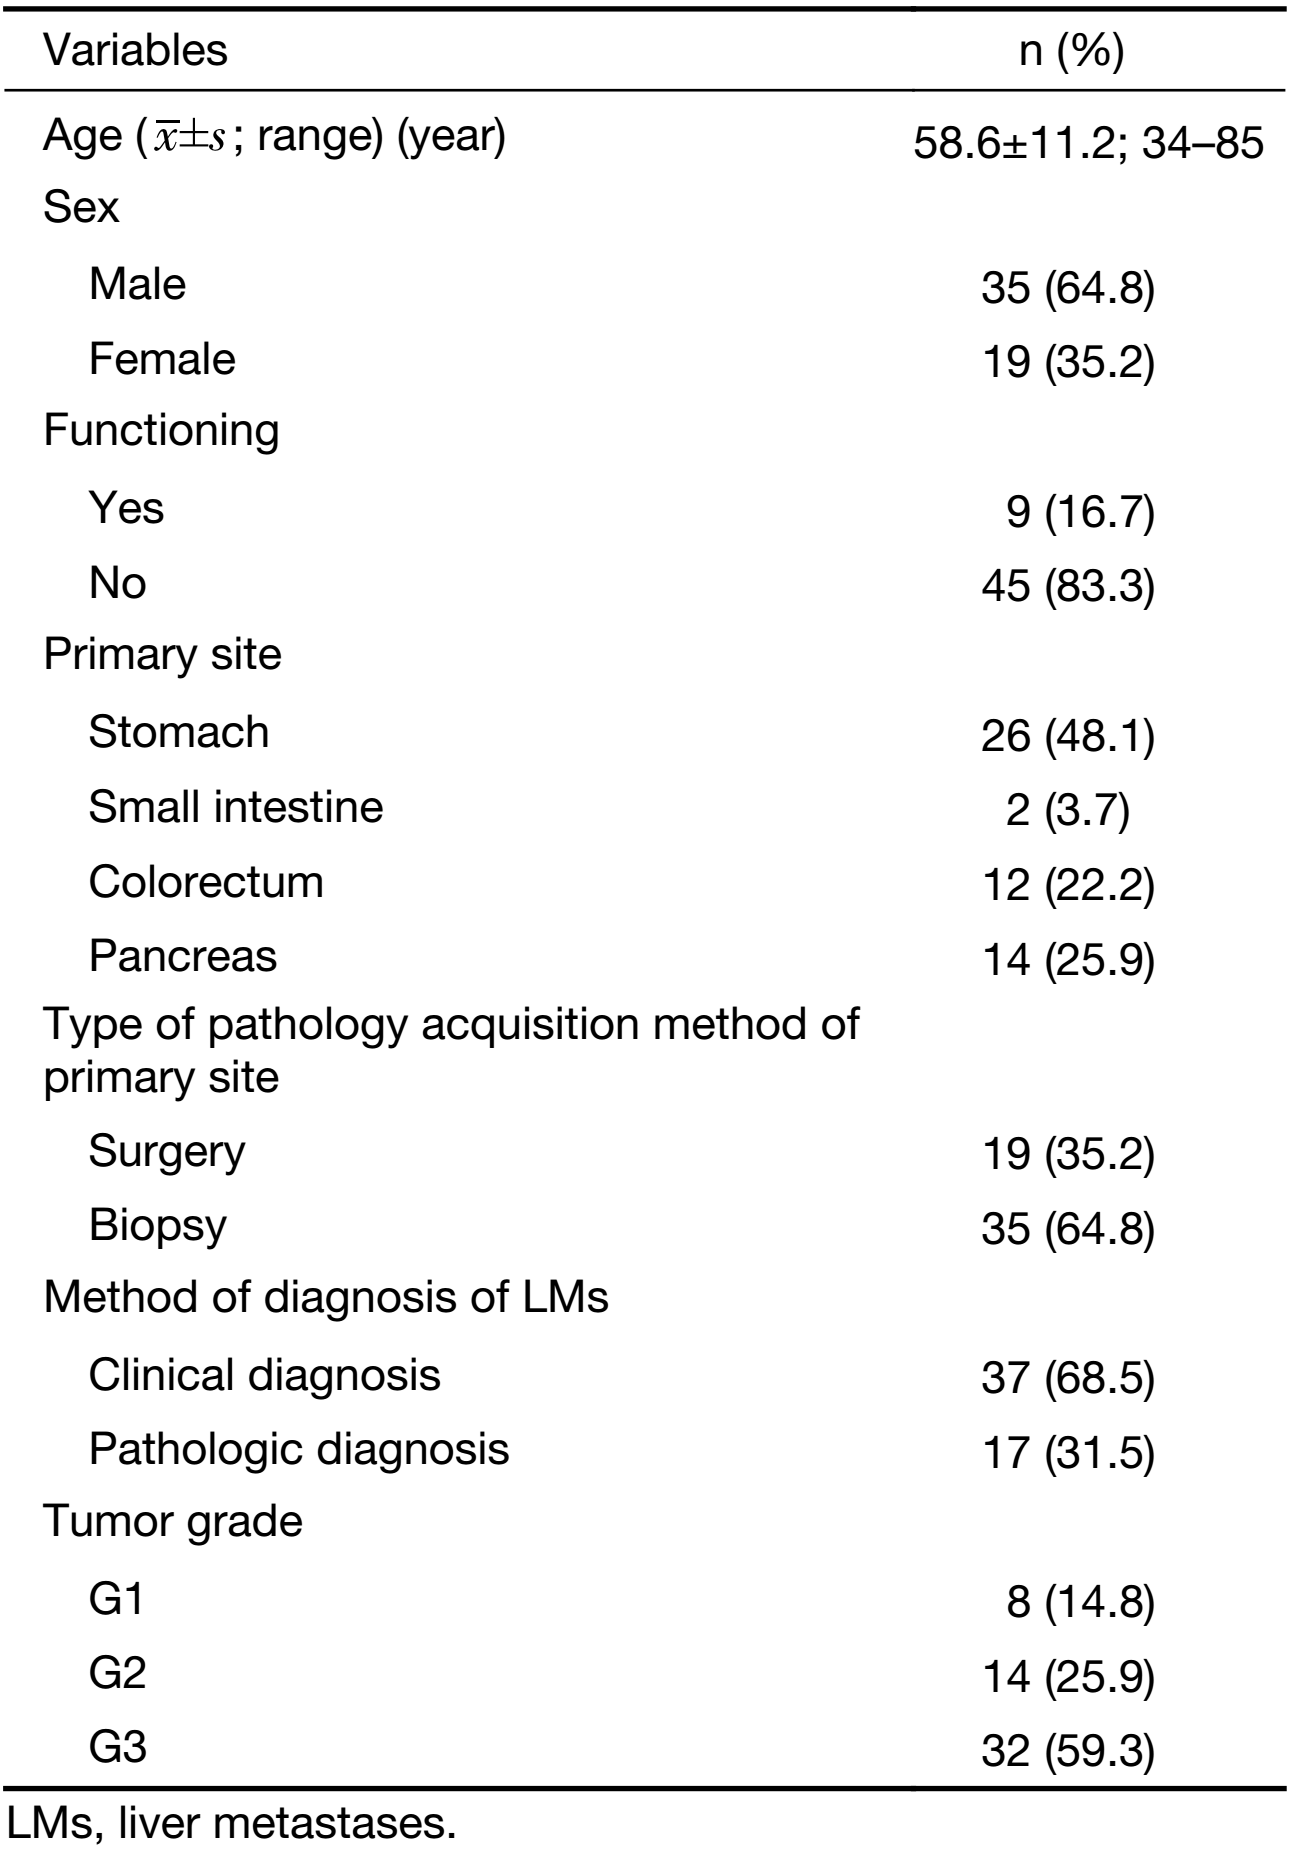

A total of 129 patients with pathologically proven NEN LMs who had undergone CT examination were identified in Peking University Cancer Hospital during the study period. Of these patients, 54 fulfilled the inclusion criteria and were enrolled in the study (Figure 1). The clinical characteristics of the patients are listed in Table 1.

The qualitative image analyses of LMs of well- and poorly-differentiated GEP-NENs are summarized in Table 2. The distribution and shape of tumors were not significantly different between the two groups (P=0.761 and 0.508). All the LMs of GEP-NENs were mainly diffused with a round-oval shape. More feeding arteries and intratumoral neovascularity were found in LMs of poorly-differentiated GEP-NENs than in LMs of well-differentiated GEP-NENs (P=0.005 and 0.003). With regard to the enhancement area, there was no significant difference (P=0.050), and the enhancement pattern was not significantly different (P=0.477). Lymphadenopathy was statistically significant in differentiating LMs of well-differentiated GEP-NENs from poorly-differentiated GEP-NENs (P<0.001), with lymphadenopathy occurring more often in poorly-differentiated GEP-NENs. Representative cases are shown in Figures 2 and 3.